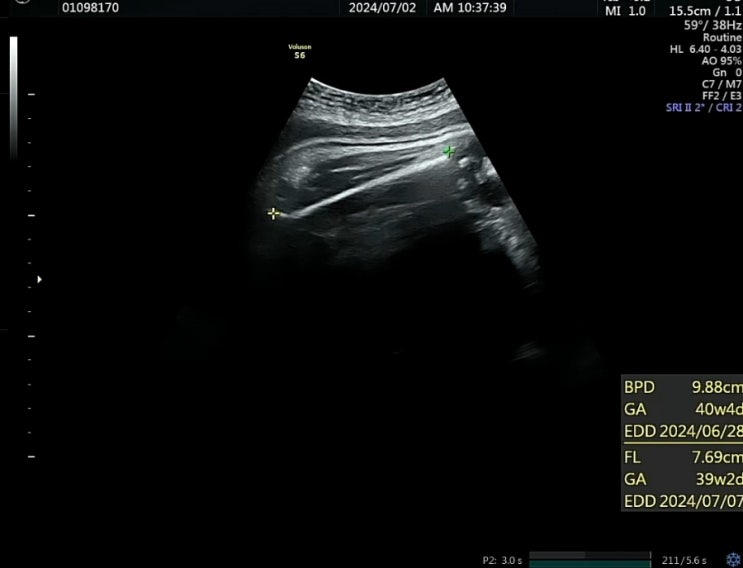

37주 6일

드디어 방빼는 날 잡았어요. 7월 4일 유도 분만 하기로 했어요. 태동 검사 하고 진료실 가서 내진검사 하니...